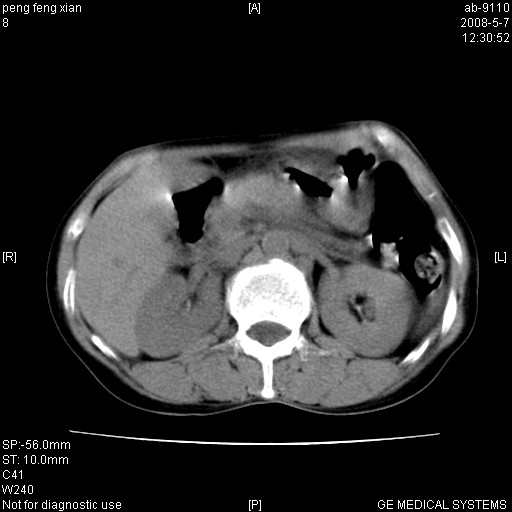

女,56岁。b超左一腹包块,考虑胃肠道肿瘤。

胃壁增厚,左前胸壁局限性隆起,考虑胃癌可能性大,建议做胃镜

典型胃癌胰体尾部受侵。

胃底占位待出;右肾结石?

胃体部胃壁增厚,不均匀性强化,与胰腺分解欠情.

考虑:胃癌,胰腺受侵待除外.

鉴别:胃淋巴瘤(强化不明显)

建议:胃镜检查.